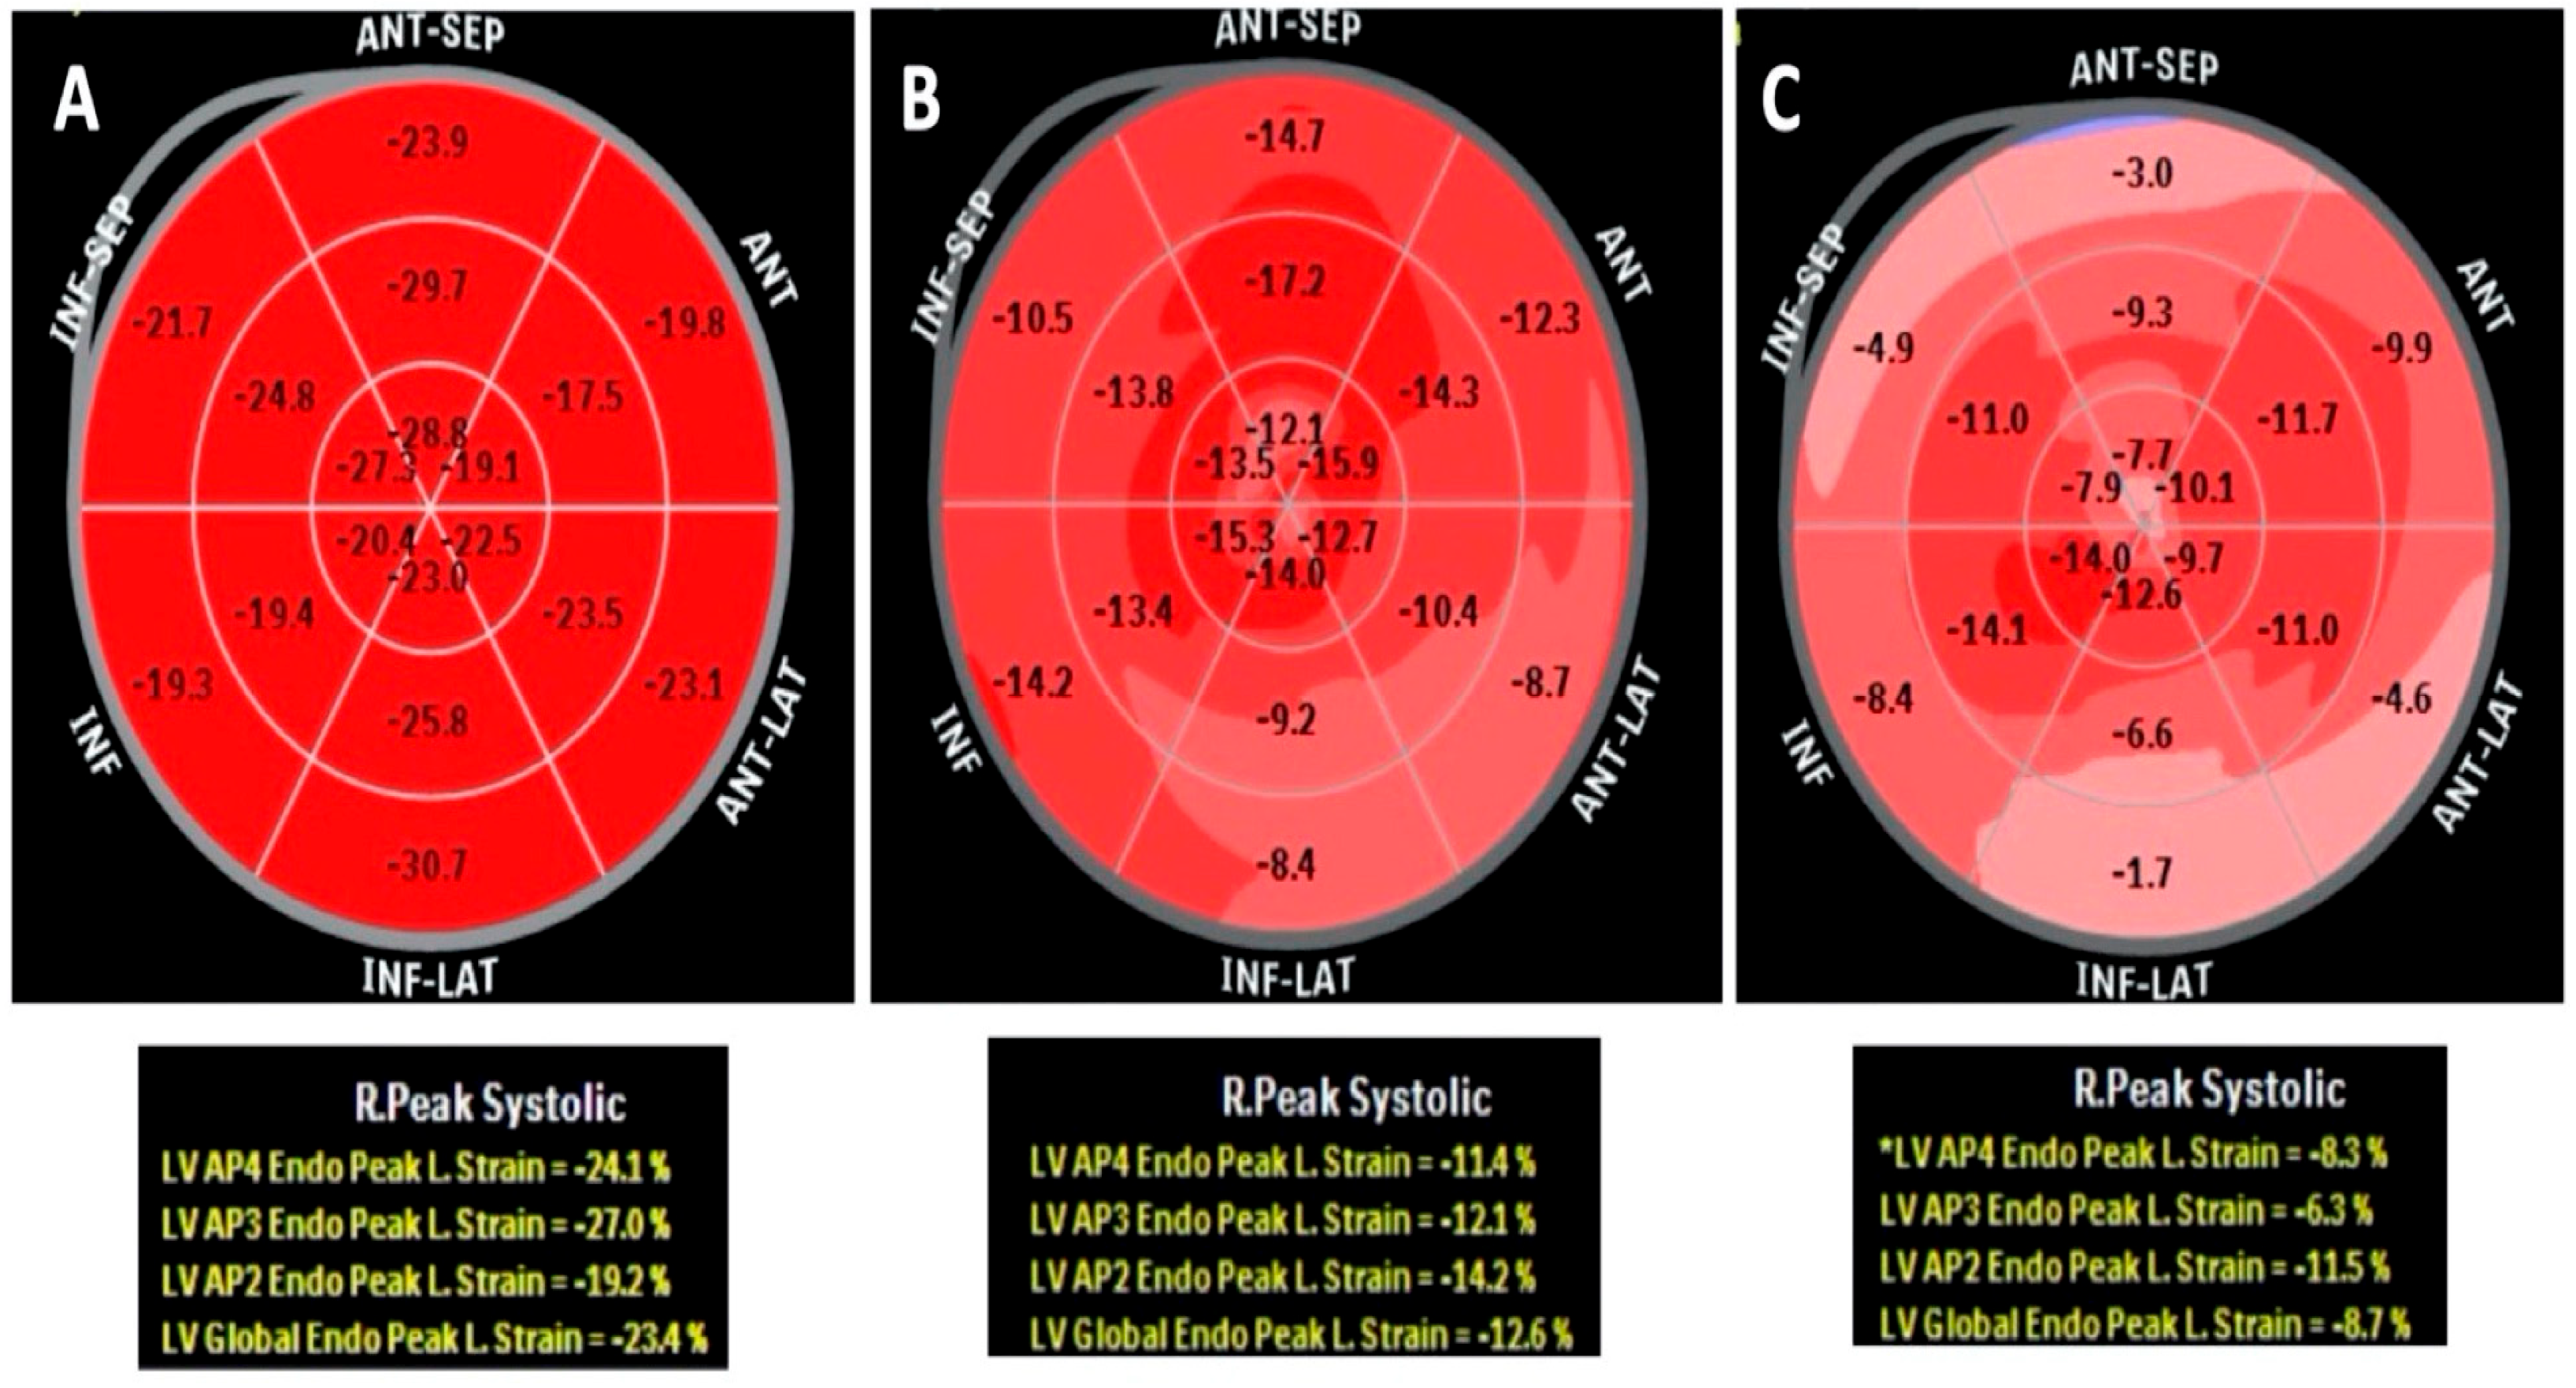

- Tsuruda, T.; Nakada, H.; Yamamura, Y.; Matsuura, Y.; Ogata, M.; Tanaka, M.; Suiko, Y.; Komaki, S.; Tanaka, H.; Moribayashi, K.; et al. Basal inferoseptal segment is highly susceptible to deformation in the clinical spectrum of transthyretin-derived amyloid cardiomyopathy. Eur. Heart J. Open 2024, 4, oeae076. [Google Scholar] [CrossRef]